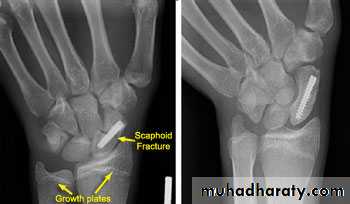

It is caused by fall on out stretched hands ; the most important point in scaphoid is its blood supply inter the bone from distal to proximal direction , so the blood supply is decreased from distal to proximal ; this fact explain why only 1% of the fracture in the distal third of scaphoid , 20% of the fract. In the middle third and 40% of the proximal third fract. Will develop avascular necrosis and non union .Clinically : there is fullness and tenderness in the anatomical snuff box ; other diagnostic sign is that, proximal pressure along the axis of the thumb is painful .

X-ray : a-p , lateral and oblique views are all essentials . Some time recent fracture show it self only in oblique view .

Usually the fracture is transverse and through the narrowest part of the bone (the waist) , but it could be in the proximal pole or in the tubercle ; few weeks after injury the fracture will be more obvious.

Displaced fracture : treatment by open reduction and fixation by compression screw .